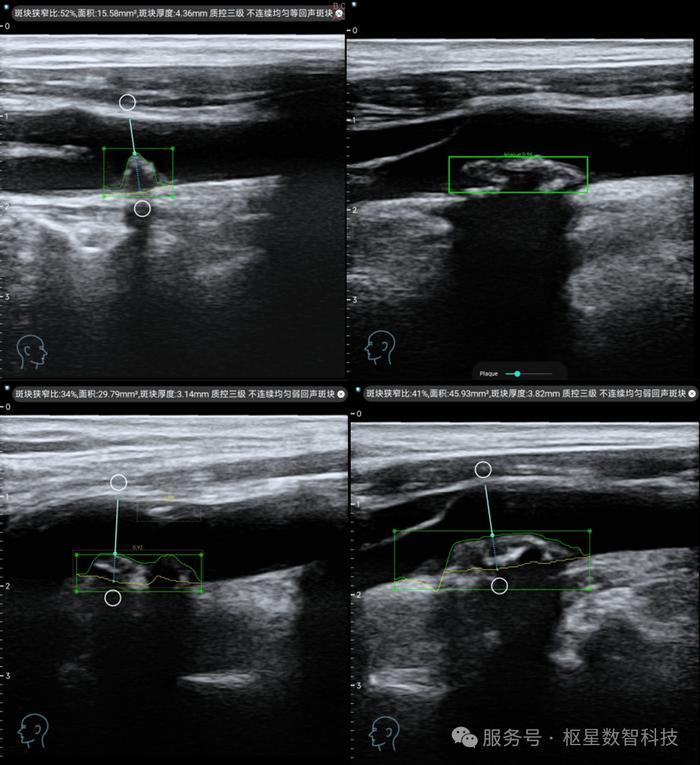

1. 智能影像分析

基于深度學習算法,實現對頸動脈超聲影像的實時分析,自動完成血管內中膜厚度測量、斑塊識別與量化評估,診斷準確率達到三甲醫院專家水平。